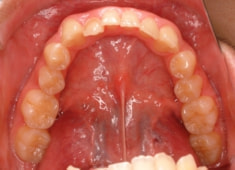

治療前

症例紹介

反対咬合+左上3番高位埋伏

(受け口+左上3番目の永久歯が上顎の中に埋まったままはえてきていない)

治療法:フルパッシブブラケット:T21

解説:残存している左上乳犬歯Cを抜歯し、そのスペースに左上3番を誘導しました。Cと犬歯ではスペースが足りないので、前歯をアドバンスさせ、反対咬合を同時に解消しております。